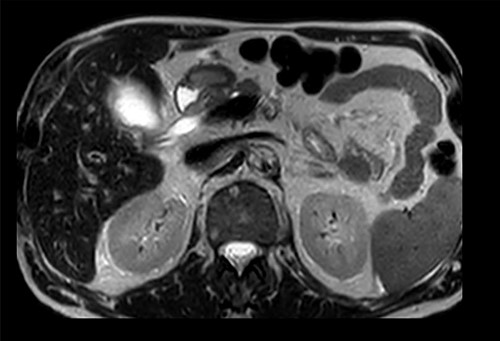

Axial section of preoperative CT abdomen from initial presentation showing thickened gallbladder with pericholecystic fluid; duplicated gallbladder evident, initially thought to be Phrygian cap sign.

Preoperative T2-weighted MRCP; double cystic ducts seen upon retrospective review of images post cholecystectomy.